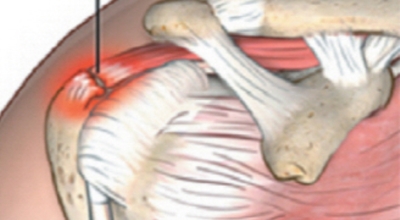

어깨 회전근개파열 치료방법 비수술적인 방법으로 핌스치료방법이 있습니다. 근본적인 회복에 목적을 둔 치료방법으로 초음파와 영상유도하에 정확성과 안정성을 입증받은 치료입니다. 30분 정도의 치료시간으로 부분마취로 간단하게 치료받을 수 있답니다.